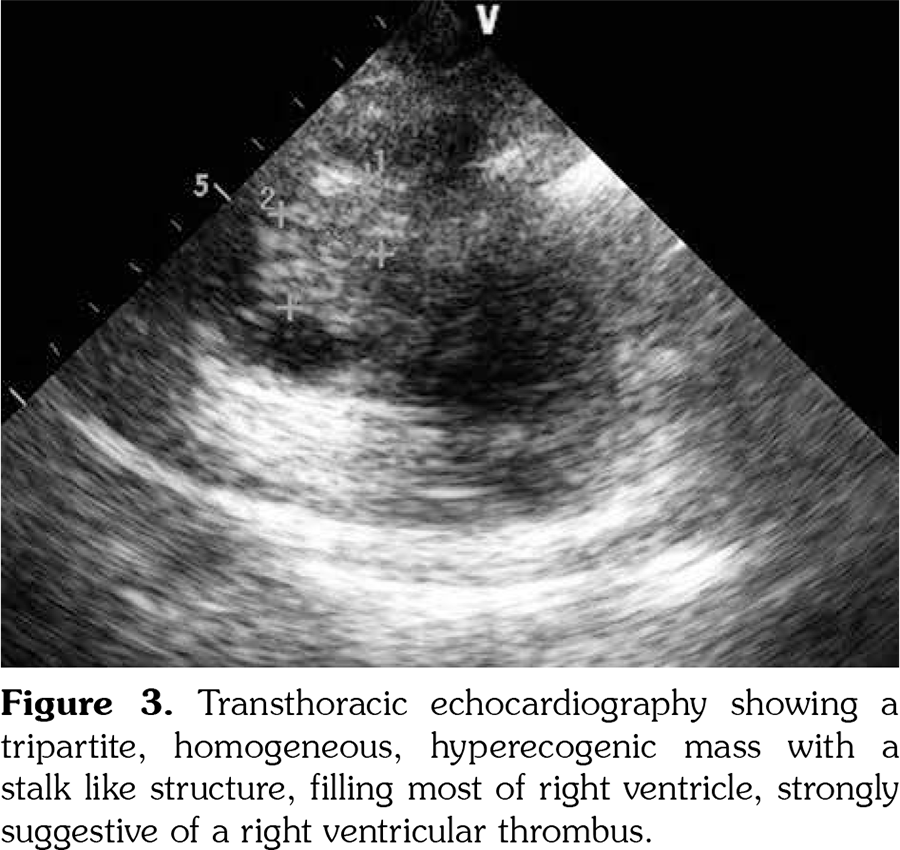

On admission, body temperature was 38.5°C. The patient had tachypnea, dyspnea, tachycardia, decrease of breath sounds in the basal regions of both lungs, and few crackling rales were heard in the left lung field. There was nearly total loss of vision in the right eye and 40% loss of vision in the left eye. Chest radiograph revealed a large left parahilar mass and peripheral infiltration (Figure 1). Computed tomography (CT) angiogram revealed two aneurysmal dilatations originating from the intraparenchymal branches of the left pulmonary artery (18x26 mm, 31x20 mm). Peripheral infarct areas were seen in basal fields of both lungs, and pulmonary embolism was present in the intraparenchymal branches of the right pulmonary artery (Figure 2). Concurrent transthoracic echocardiography showed a tripartite homogeneous hyperechogenic mass with a stalk-like structure, measuring 25x27 mm, filling most of the right ventricle, strongly suggestive of a right ventricular thrombus (Figure 3). The right ventricular pressure was within normal limits, thereby excluding pulmonary hypertension. Doppler ultrasound of lower extremities was unremarkable.